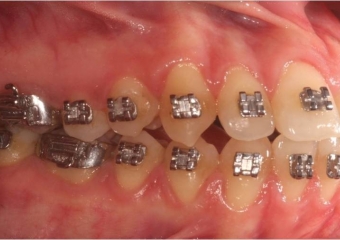

Mordida inicial